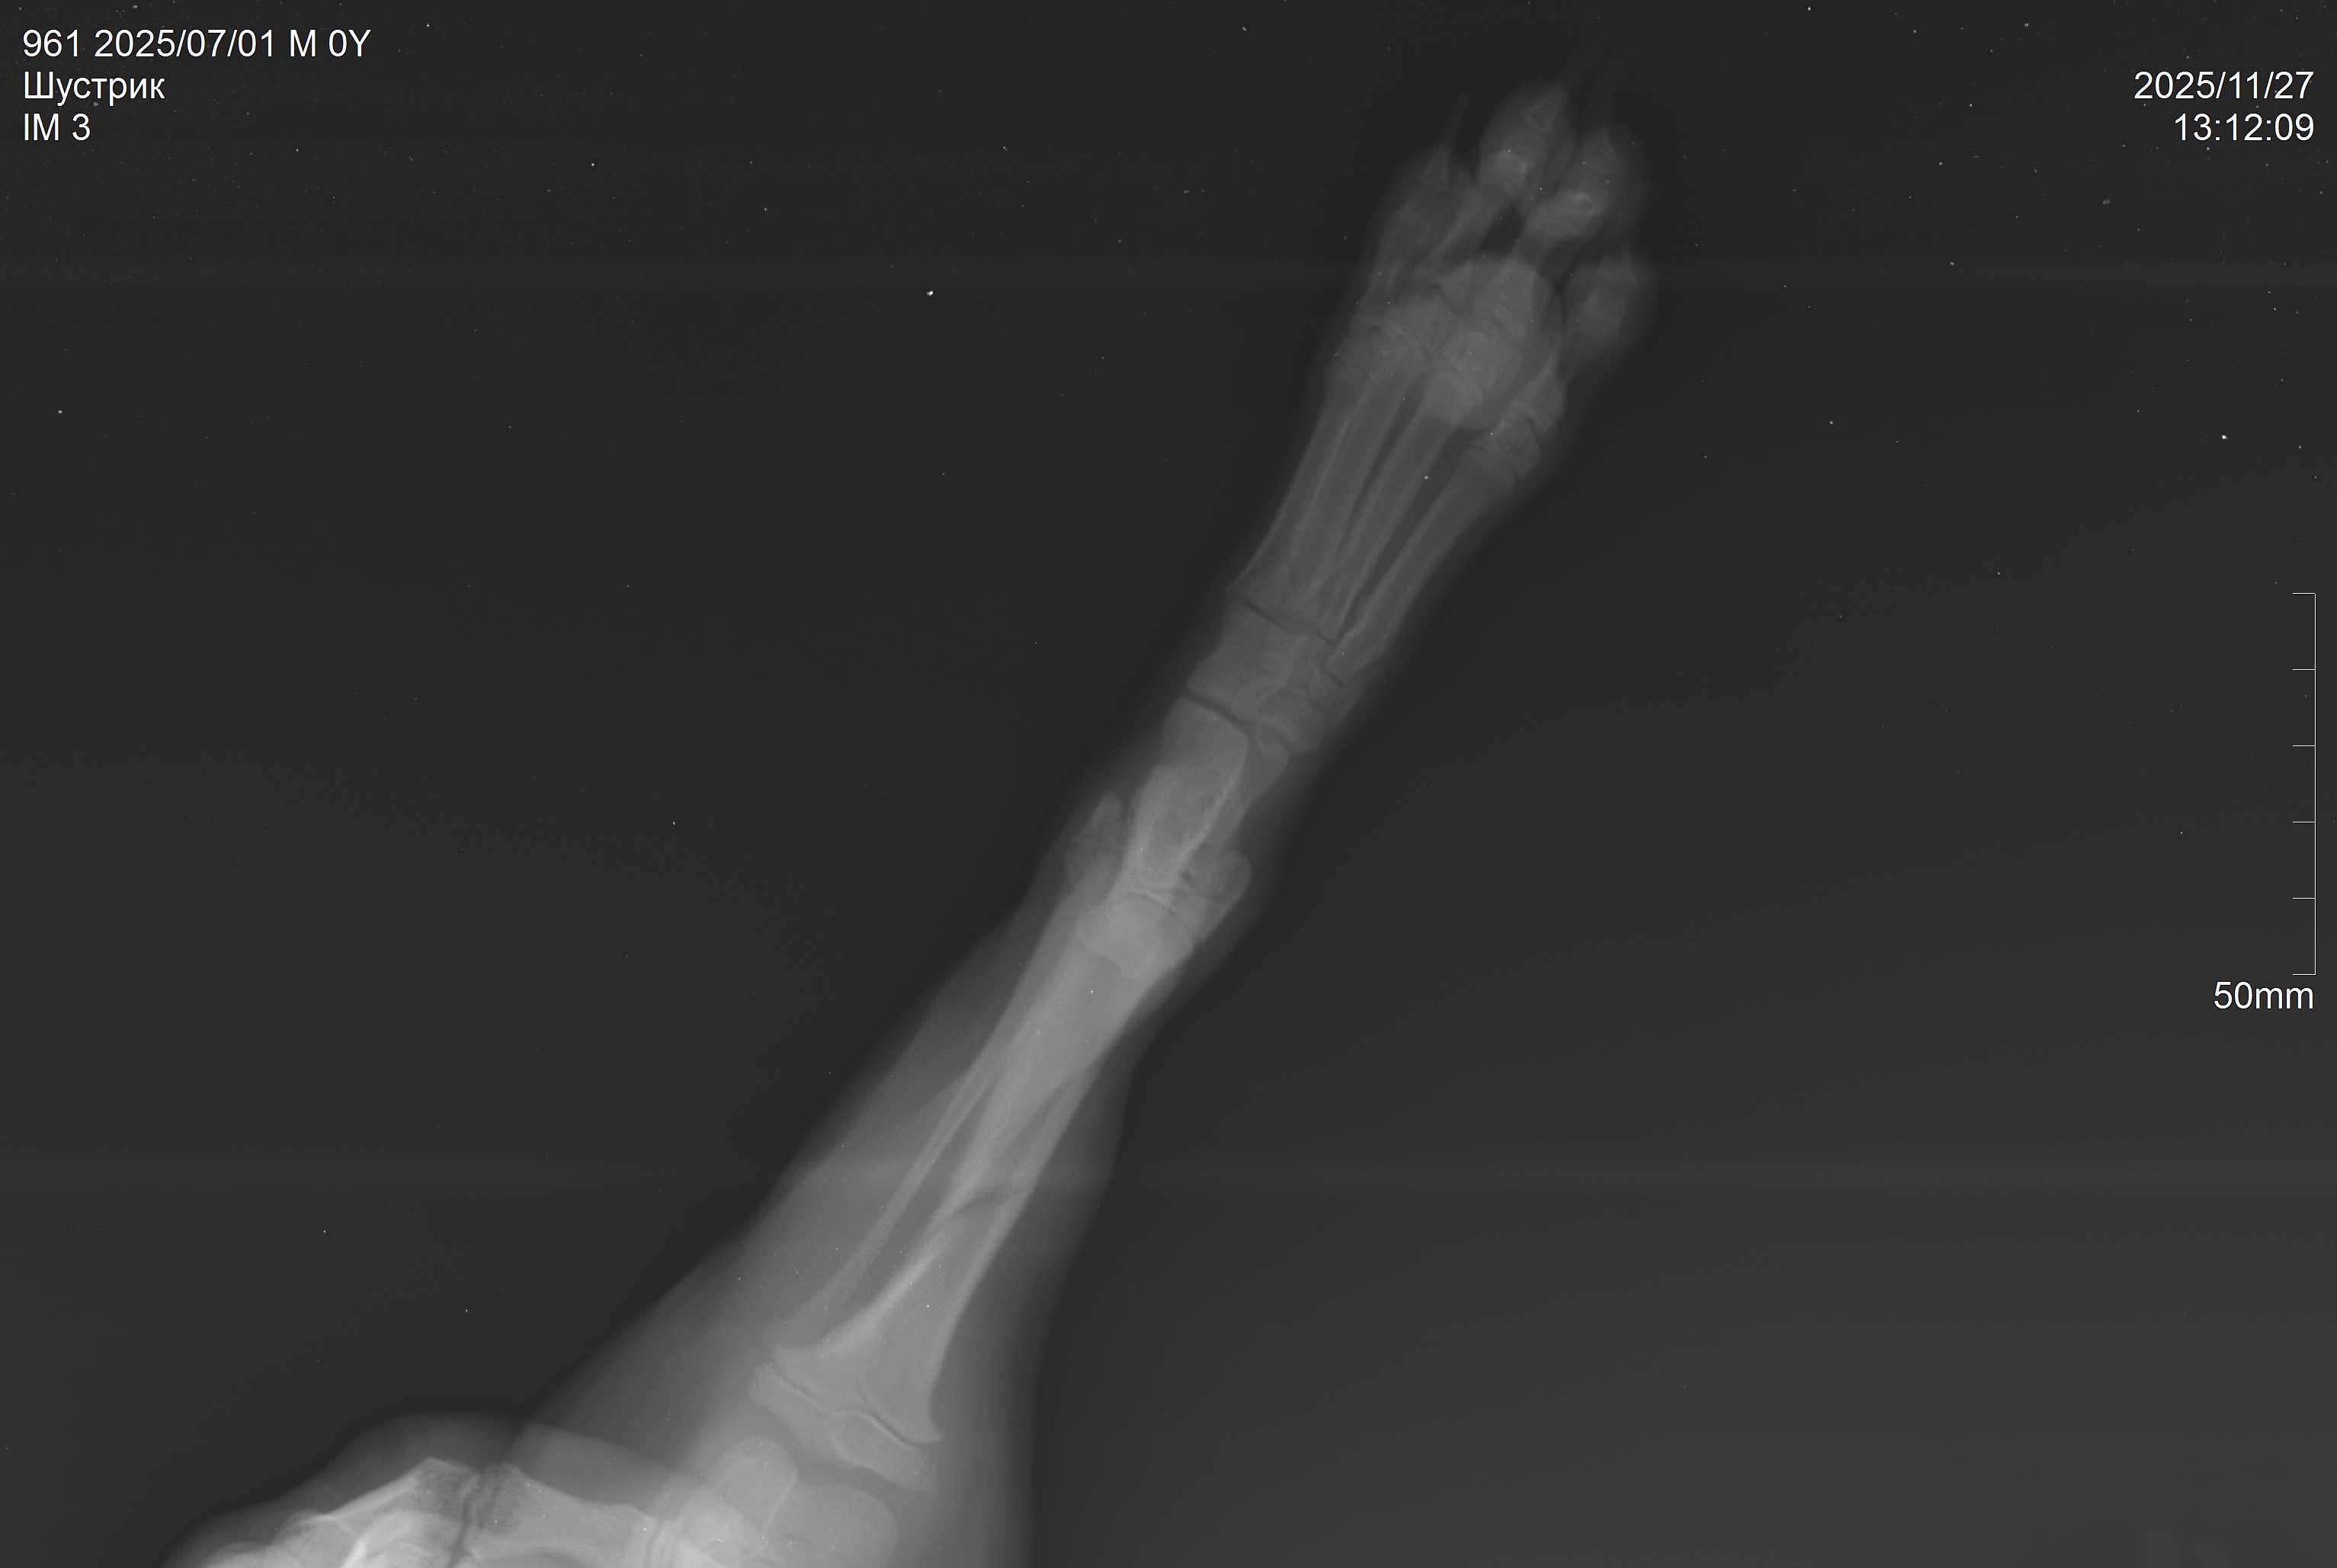

На прием в участковую Вет. лечебницу по ул. Огородная обратилась владелица щенка по кличке Шустрик с жалобами на снижение активности и хромоту на левую тазовую конечность. После клинического осмотра и сбора анамнеза Шустрику была назначена рентген-диагностика, благодаря которой был поставлен диагноз: косой оскольчатый перелом большеберцовой кости.

Большеберцовая кость (тибиум) - одна из основных костей голени у собак, обеспечивающая поддержку и движению. У щенков переломы этой кости — ситуация довольно частая, особенно у активных или неосторожных животных. Правильное и своевременное лечение имеет решающее значение для полного восстановления функции конечности. Шустрику была назначена консультация и осмотр травматолога для последующего проведения остеосинтеза кости.